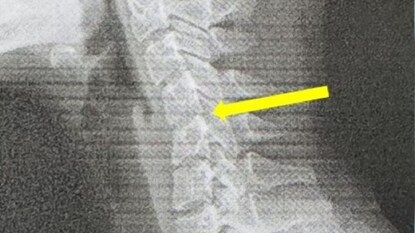

পরীক্ষার সময় এক্স-রেতে দেখা যায়, তাঁর সারভাইক্যাল স্পাইন (ঘাড়ের হাড়) স্বাভাবিক ভাঁজ হারিয়ে ফেলেছে। কিছু জায়গায় কশেরুকার (vertebrae) মধ্যে স্লিপ সরে গেছে। এই অবস্থা সাধারণত “টেক্সট নেক” (Text Neck) নামে পরিচিত, যা অকালেই সারভাইক্যাল ডিজেনারেশন (ঘাড়ের হাড়ের ক্ষয়) এর লক্ষণ হতে পারে।